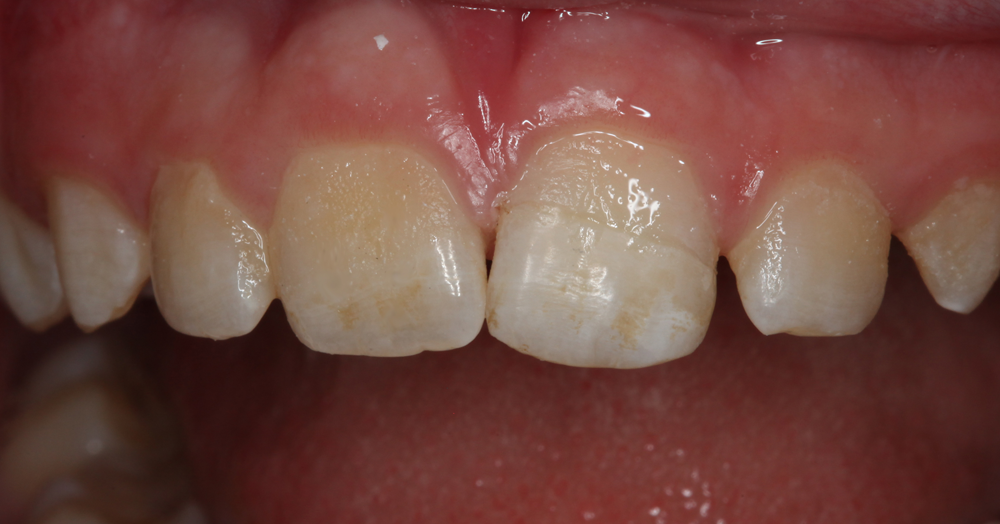

Fortunately, the patient’s mother had retained the missing, fractured tooth segment (Fig. 3). Therefore, the treatment plan discussed with and accepted by the patient’s parents involved reattaching the fractured tooth segment using a universal dual-cure adhesive resin cement, G-CEM LinkForce, after which a compactable universal nano-hybrid composite, G-ænial Sculpt would be placed to directly veneer the facial and palatal surfaces of the tooth to mask the fracture line (Fig. 4).

Fig. 3 Fig. 4